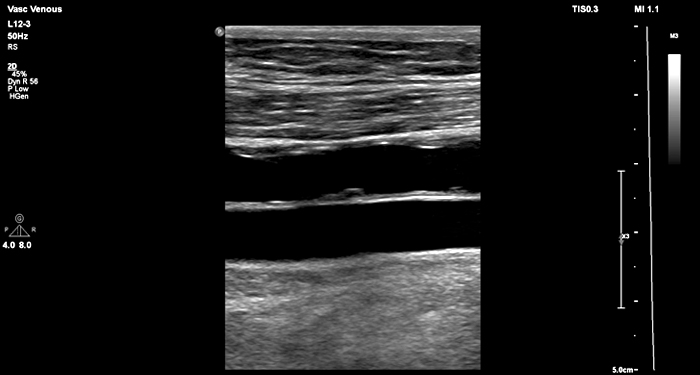

At the touch of a button, the new MaxVue high-definition display brings extraordinary visualisation of anatomy with 1,179,648 additional image pixels compared to a standard 4:3 display format mode. MaxVue enhances ultrasound viewing during interventional procedures and provides 38% more viewing area to optimise the display of dual, side/side, biplane, and scrolling imaging modes.

MaxVue offers a 38% greater viewing area.